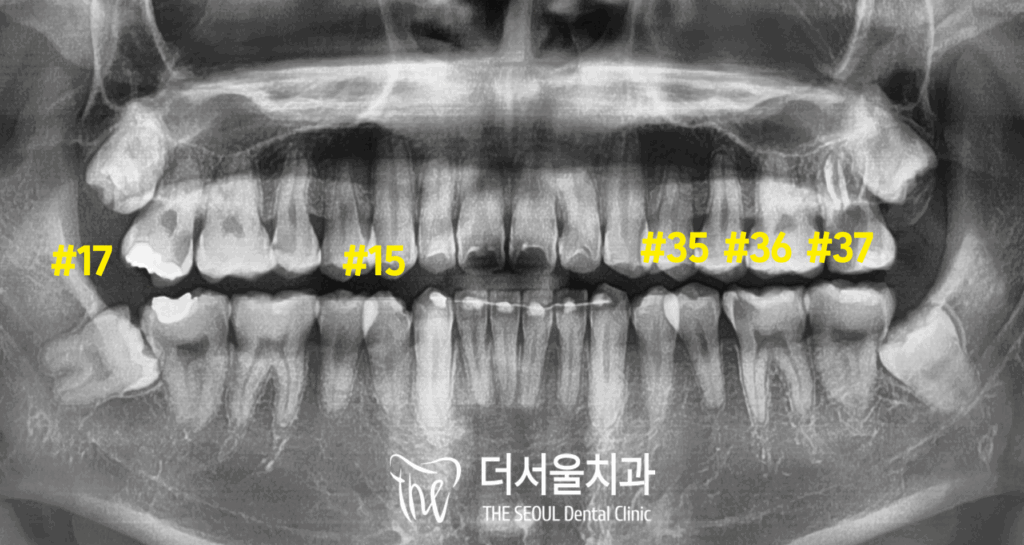

1. 초진

충치 검진을 받고 싶다며 오셨던 분입니다.

치과에 오신지 약 1년 정도 흘렀다는데요.

요즘 들어 어금니 욱신거리고 찌릿하다며

인터넷 검색 후 내원하셨습니다.

검진을 진행하여 확인해 보니,

다수의 우식이 발견되었습니다.

주로 구치부에 분포해 있었는데요.

미세한 틈 사이에 음식 찌꺼기가 잘 끼지 않고

세균 번식으로 이어져 이가 썩었습니다.

상악의 경우 눈에 잘 띄지 않는

인접면에도 충치가 발견되었는데요.

다행히 깊게 진행되진 않았기에

이곳은 비교적 간단히 개선을 할 수 있겠네요.

나머지 큰 어금니들은 신경치료가 필요할 정도로

상황이 좋지만은 않았습니다.

주로 오른쪽 윗니, 왼쪽 아랫니가 썩어 있었습니다.

검진을 진행해 보니 양쪽 모두

신경치료(엔도)가 필요한 상황이었는데요.

우선 심한 통증을 느끼고 있던 왼쪽 아랫니부터

순차적인 진료를 도와드리기로 했습니다.

비교적 깊게 썩어 있는 첫 번째 큰 어금니는

엔도를 진행하기로 했으며,

두 번째 어금니와 소구치는

인레이라는 부분 보철로

개선을 도와드리기로 했습니다.